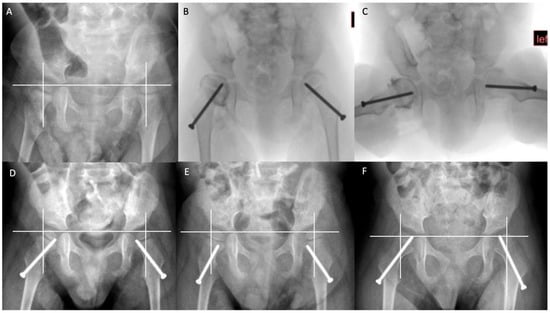

13. Guided Growth and Proximal Femoral Geometry in CPHD

14. Bony Reconstructive Surgery for CPHD

15. Bilateral Surgery for Unilateral Hip Displacement?